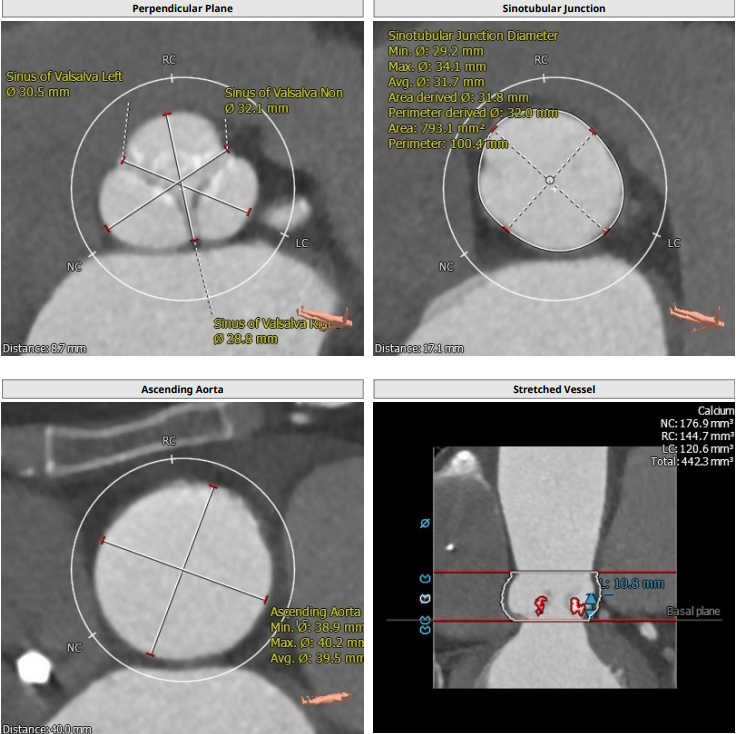

对于TAVR准备阶段,以国内现在大规模使用的自展瓣为例,通常需要使用20F的大鞘,CT分析入路情况是保证手术安全的前提,除常规需要5.5甚至是6.0以上的股动脉内径外,股动脉的钙化情况,proglider的熟练使用都是避免血管相关并发症的前提,当然,术中出现入路并发症,也需丰富的经验来判断风险,手术是否能继续,术前需要准备什么耗材都是处理入路并发症的前提,广东省人民医院TAVR团队术前除常规耗材外,还常备外周8*60高压球囊及外周支架以备不时之需。

根部解剖: